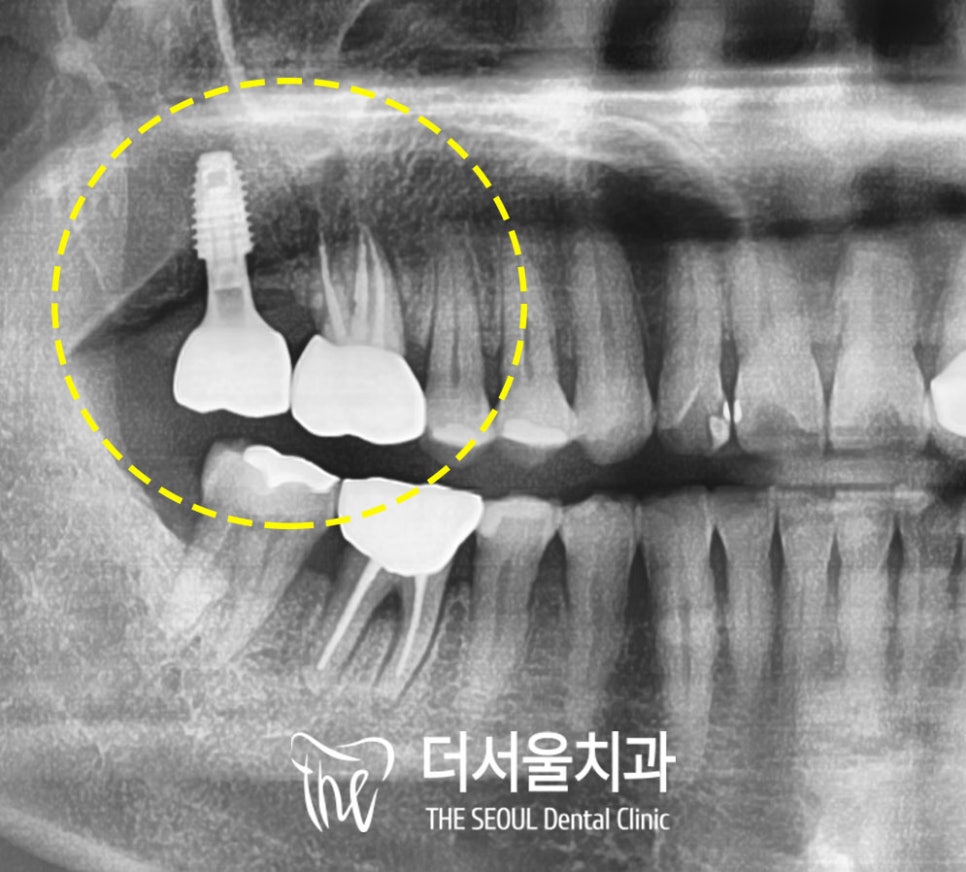

근관의 끝부분까지 잘 수복됐고

픽스처도 치조골에 잘 심어진 것을

확인할 수 있습니다.

2~3개월 정도

인공치근이 치조골 내에서

단단하게 유착되면

1:1 맞춤형 보철물을 씌워줍니다.

더서울에서는 지르코니아 라고 하는

강도가 높고 심미성이 우수한 보철을

구강 구조와 교합관계에 맞춰

맞춤형으로 제작합니다.

이렇게 문제가 됐던

두 개의 어금니를 치료했습니다.